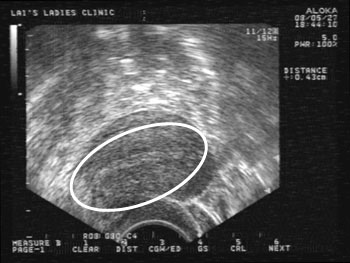

世界首例!PGD 挽救週邊漸凍人「生」機,世界第一例運用胚胎著床前基因診斷克服遺傳性腓骨肌萎縮症第IIE型,而順利受孕成功的案例。為了讓白先生能一圓生子夢, 白先生 帶著太太找到博元婦產科蔡鋒博醫師求診,於是博元婦產科蔡鋒博醫師做第三代試管嬰兒PGD胚胎著床前基因診斷 htt...